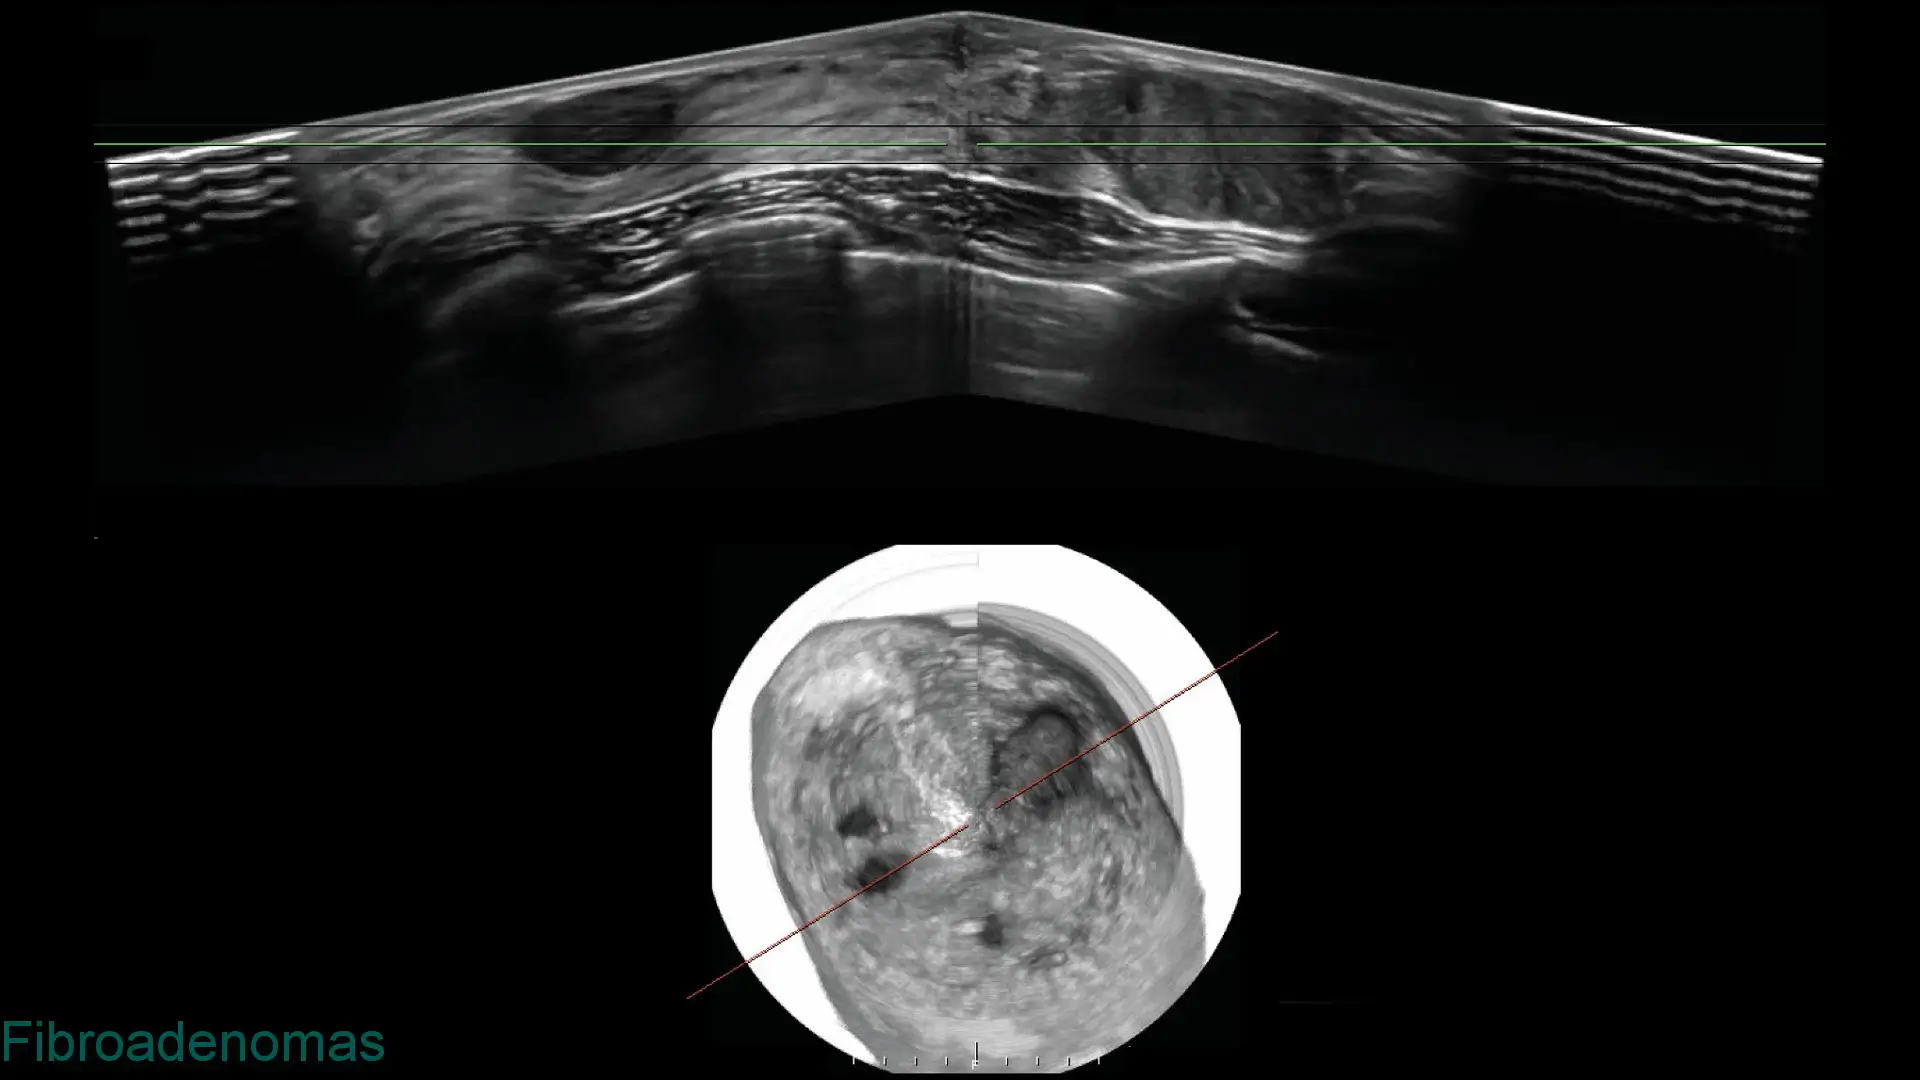

Explore clinical breast ultrasound images captured with SOFIA, showcasing various tissue types and conditions with exceptional clarity.